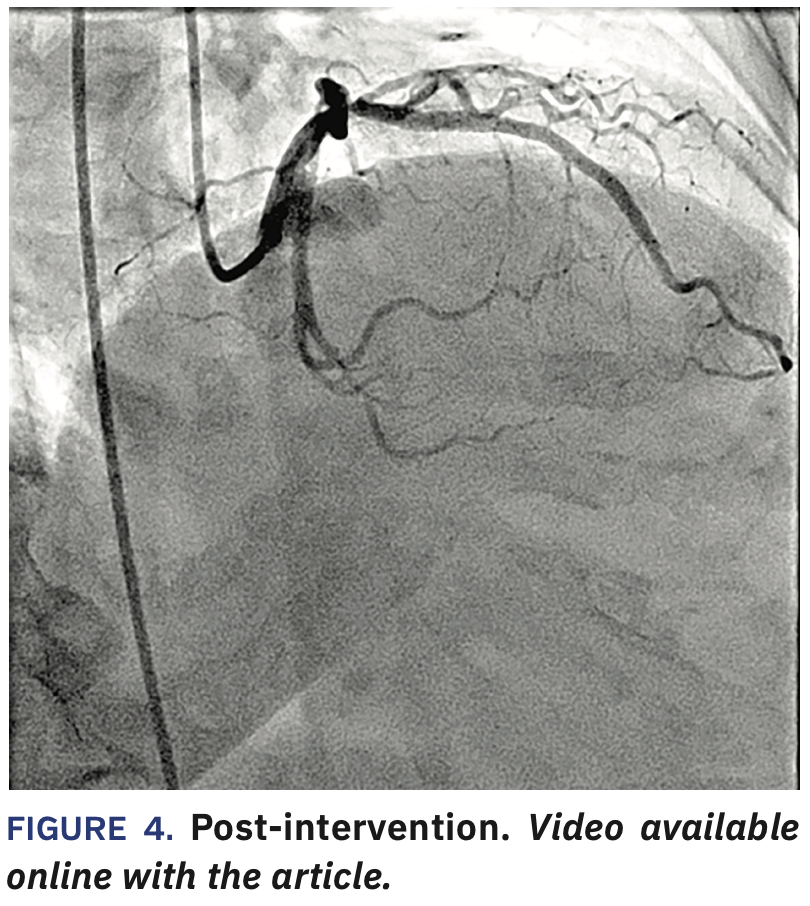

The JR4 was used to get left ventricular end diastolic pressure. The sheath was upsized to a 6 Fr size for the intervention and after giving heparin and 500 mcg nicardipine, a JL4 guide and Sion blue wire (Asahi Intecc) were used to cross the lesion. A 2.0 x 20 mm Apex balloon (Boston Scientific) was used to predilate the proximal to mid left anterior descending (LAD) coronary artery (up to 14-18 atmospheres [atm] for 7 seconds x3). 2.50 x 38 mm Synergy XD and 3.00 x 20 mm Synergy XD stents were placed (14 atm x1 and 14 atm x1), respectively in the mid and proximal vessel, followed by 2.50 x 20 mm (20 atm for 5 seconds x3) and 3.50 x 20 mm NC Apex (16 atm for 9 seconds x1) balloons. This was followed by an intravascular ultrasound (IVUS) run (Figures 2-3), resulting in further balloon dilatation with 2.75 x 15 mm (up to 16-25 atm for 7-11 seconds x4) and 3.75 x 15 mm Euphora NC (up to 18-25 atm for 7-8 seconds) (Medtronic) balloons in order to further dilate the under-expanded sections. We used CLEARstent Live (Siemens Healthineers) to help position the NC balloons. Final angiography showed a good result (Figure 4). The patient underwent closure with an Angio-Seal (Terumo) and she was placed on aspirin and ticagrelor, given the extent of stenting.

Dose area product (DAP) used in the new lab (Siemens ARTIS icono System) was 7454.21 cGycm2 versus 11740.30 cGycm2, or about 37% less compared to an older lab from a different company for a similar-sized patient and a similar intervention.*